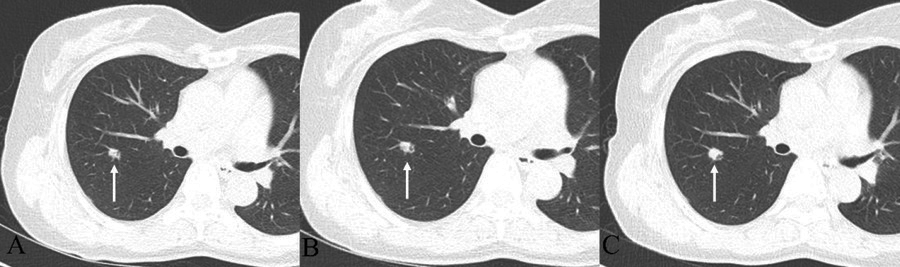

Figure 2

Chest CT with follow up. (A) 9-mm lobulated nodule with an internal air-bronchogram in the right upper lobe. (B) After 1 year, the nodule shows a minimal increase in size, 9 to 10 mm. (C) After 2 years later from the initial chest CT, the nodule changes from 10 to 13 mm in size, and the somewhat dilated internal bronchus are detected.